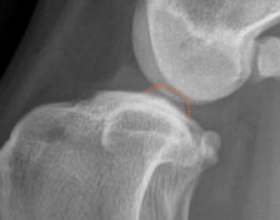

TPA calculation has some prerequisites that must be fulfilled, these are:

The Stifle and Tarsus must be 90°flexed;

Functional Tibial line must be formed by connecting

Centre of Talus

The centre of intercondylar eminences shown in Fig. 1;

The Medial Tibial Plateau line should be drawn using the first two.

Following the identification of points of interests, and drawing of the lines of interest, i.e. the Functional Tibial Line (FTL) and the Medial Tibial Plateau Line (MTPL), another line is drawn such that the relation of new line and the FTL is 90°. Tibial plateau angle is the angle between this new line and the MTPL; this is shown in Fig. 3.